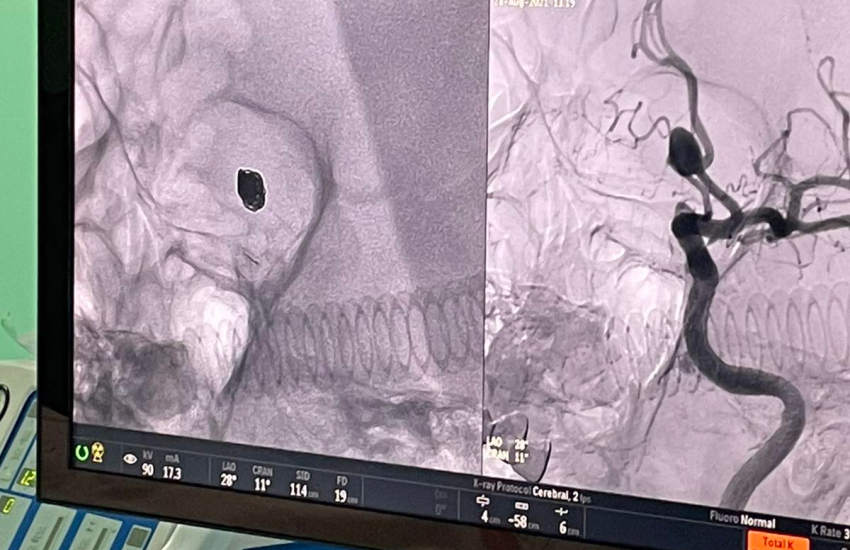

Цими днями наші лікарі відділення інтервенційної радіології разом з провідним фахівцем з ендоваскулярної нейрохірургії Чередниченко Юрієм Віталійовичем, к.мед.н., лікарем-нейрохірургом КП «Дніпропетровська обласна клінічна лікарня імені І.І. Мечникова» Дніпропетровської обласної ради» та за підтримки компаній Medtronic успішно виконали ендоваскулярне виключення мікроспіралями аневризми артерії головного мозку, попередивши інсульт у пацієнта.

За словами завідувача відділення інтервенційної радіології Черкаської обласної лікарні Паляничка Дмитра Андрійовича, операцію було виконано найбезпечнішим і сучасним способом, зробивши прокол артерії кисті пацієнта, через який хірурги потрапили до цільової судини в головному мозку та імплантували мікроспіралі, вилучивши аневризму з кровообігу та попередивши її розрив та інсульт. Хірург зауважив, що такі операції, на відміну від відкритих, з трепанацією черепу, в рази знижують ризик як самої операції, так і післяопераційних ускладнень. Вже через пару годин після операції пацієнт повернувся до звичайного життя та був виписаний на другу добу додому.